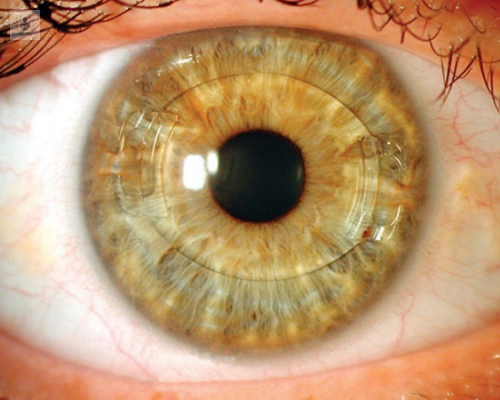

Lentes Intraoculares Suturada a Sulcus Visioncore Cl nica outlet, Reposicionamiento intercambio de lentes intraoculares outlet, Qu son los lentes intraoculares Como Cuidar Los Ojos outlet, Implante de una Lente Intraocular Multifocal M PLUS outlet, Visian ICL lentes intraoculares f quicas outlet, Cirug a Presbicia lentes intraoculares Hospital Universitari outlet, Tipos de lente intraocular en la cirug a de catarata Cl nica outlet, Lente intraocular f quico cirug a que permite dejar de usar outlet, Lentes ICL o Lentes Intraoculares Ventajas e Indicaciones outlet, LENTES INTRAOCULARES Centro de Ojos Buenos Aires outlet, Implante de lentes intraoculares todo lo que debes saber outlet, Todos sobre la operaci n de cataratas con lente intraocular outlet, Cirug a refractiva con lentes intraoculares ICL rea Oftalmol gica outlet, Lentes intraoculares efectos secundarios y complicaciones Blog outlet, Lentes intraoculares para miop a outlet, Implantaci n de lente intraocular de c mara anterior outlet, Cirug a refractiva con lentes intraoculares Miranza outlet, Lentes intraoculares ICL en qu casos est n indicadas Blog D outlet, Cirug a refractiva con lentes pseudof quicas Instituto outlet, Centro Peruano del Pterigion Cirug a de CATARATA Implante de outlet, Cirug a refractiva con lentes intraoculares XR Oftalmolog a outlet, El Lente Intraocular se utiliza toda la vida Beneficios y Costo outlet, Cirug a refractiva con Lentes Intraoculares ICL en Madrid outlet, Lentes Intraoculares F quicas introducci n y complicaciones outlet, Cirug a refractiva con lentes intraoculares en Turqu a Tour for Cure outlet, Qu problemas pueden causar las lentes intraoculares outlet, Qu es una lente intraocular t rica outlet, CIRUG A CATARATA FACOEMULSIFICACION LENTE INTRAOCULAR outlet, Sorpresa refractiva por error en el c lculo de lente intraocular outlet, Precio de lentes intraoculares Operaci n de Ojos outlet, Lentes intraoculares LIO para cataratas premium asf ricas y outlet, Lente intraocular en qu consiste la operaci n y cu ndo se outlet, Lentes intraoculares en la cirug a de catarata Vista Instituto outlet, Implante de Lente Intraocular Dr Gabriel Oliveros outlet, Video Lentes intraoculares para la operaci n de miop a una outlet, Lentes intraoculares ajustables El futuro est aqu outlet, La cirug a de implante de lentes intraoculares para la presbicia outlet, Tras las lentes intraoculares m s de un 40 sufre cataratas a los outlet, Oftalmocentro San Javier outlet, Cirug a L ser Refractiva Lente Intraocular Visian ICL outlet, Sorpresa refractiva por error en el c lculo de lente intraocular outlet, Lente intraocular Cl nica oftalmol gica VISTA S nchez Tranc n outlet, Reemplazo de lente y la cirug a de las cataratas American outlet, Conoce todo sobre un lente intraocular Top Doctors outlet, Cirug a de Catarata Centro Oftalmol gico Doctores Adrogu outlet, El Hospital Mancha Centro empieza a implantar lentes intraoculares outlet, ACTUALIZACION EN LENTES INTRAOCULARES . Dra. Gloria Carretero Leon outlet, Lentes intraoculares f quicas outlet, EN QU CONSISTE LA CIRUG A DE CATARATA Instituto Oftalmol gico outlet, CAMPA A DE LENTES INTRAOCULARES ICL Vithas Eurocanarias outlet.

Cirugia de lentes intraoculares outlet